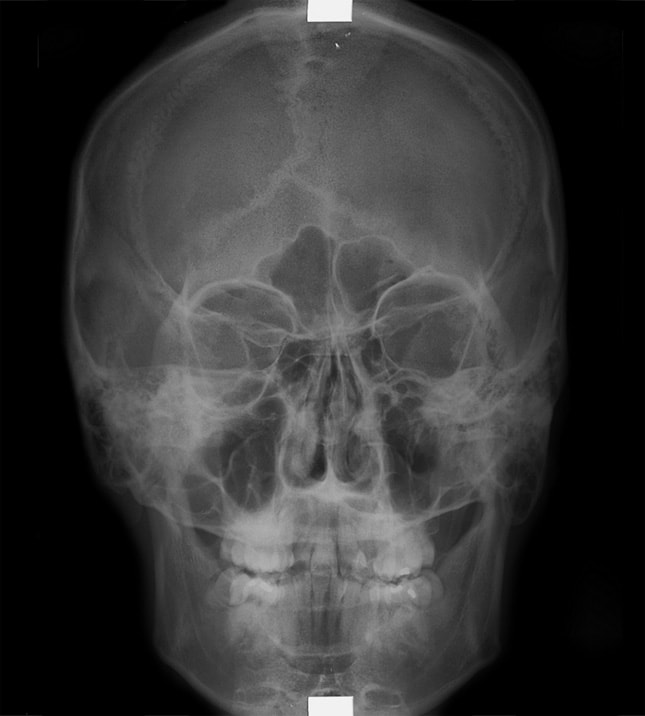

副鼻腔というのは図のように頬の奥や、目と目の間、さらに頭蓋の下にある骨に囲まれた空間です。ここに感染症をお越した状態を、副鼻腔炎といいます。